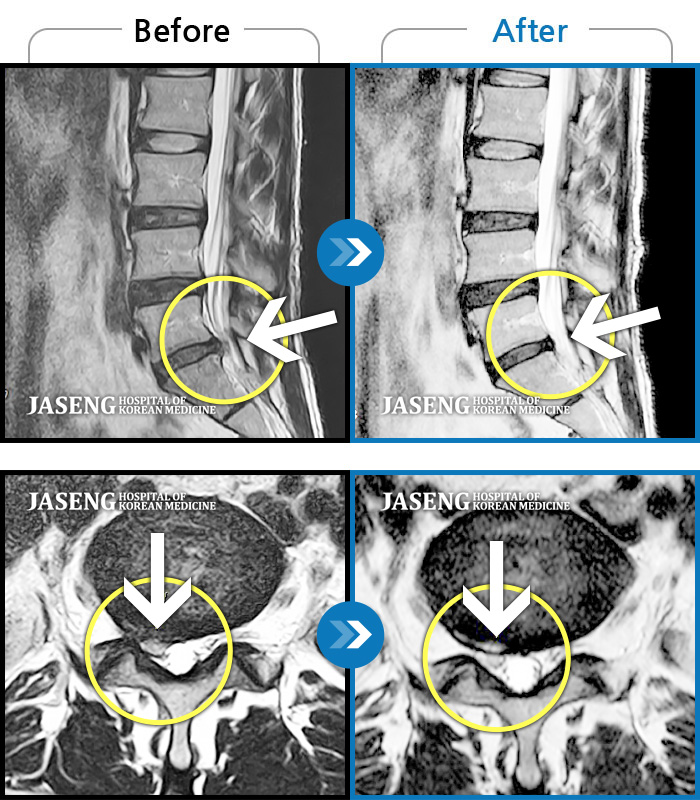

허리디스크

강남 · 이남우 원장

허리 아래쪽으로 끊어질듯한 통증과 함께 양쪽 하지 방사통으로 인해 걸을 수 가 없었음

촬영시기

2023.04.18 ~ 2023.10.20